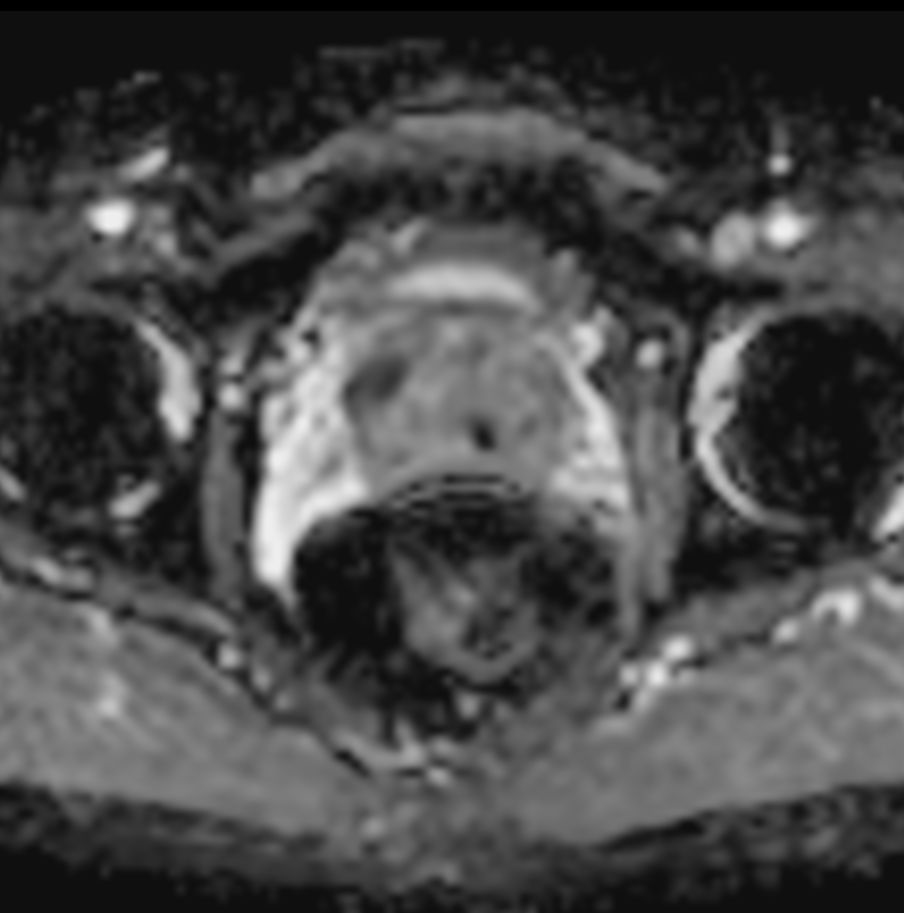

T2w SPAIR - Compressed SENSE